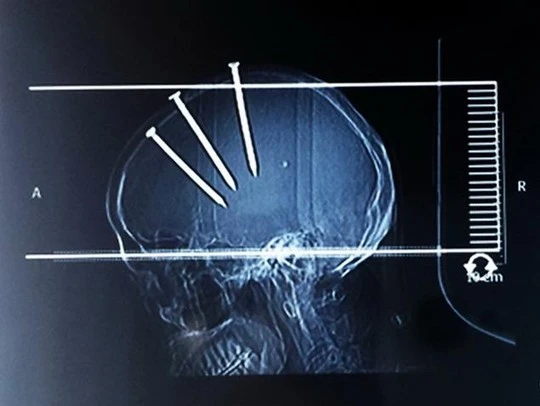

Người đàn ông 69 tuổi nói trên đến từ Haifeng, tỉnh Phúc Kiến cho hay chính ông đã tự đóng đinh vào đầu mình. Tuy nhiên, các bác sĩ cho rằng đã có người khác cố tình làm thế vì tình trạng của ông rất nguy kịch. Hình ảnh chụp X-quang cho thấy 3 cây đinh cắm sâu vào hộp sọ chỉ còn nhìn thấy được các đầu đinh bên ngoài khi ông được đưa đến bệnh viện.

3 cây đinh cắm sâu vào hộp sọ. Ảnh: REX USA